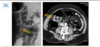

12.